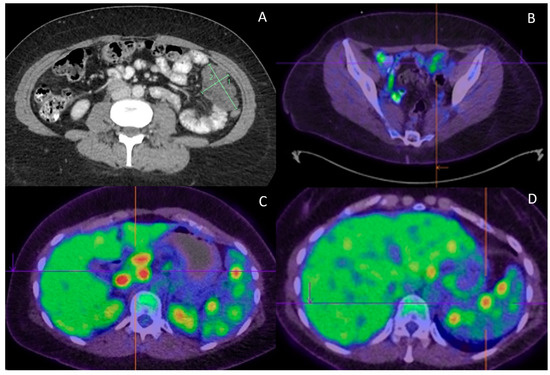

2. Case Report/Case Presentation